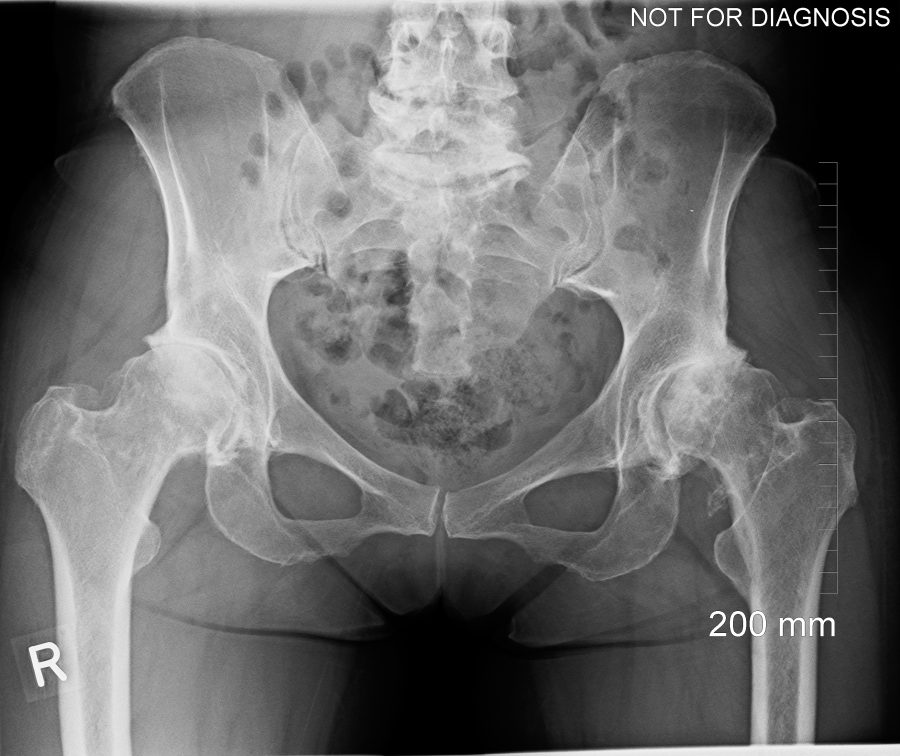

hips.jpg